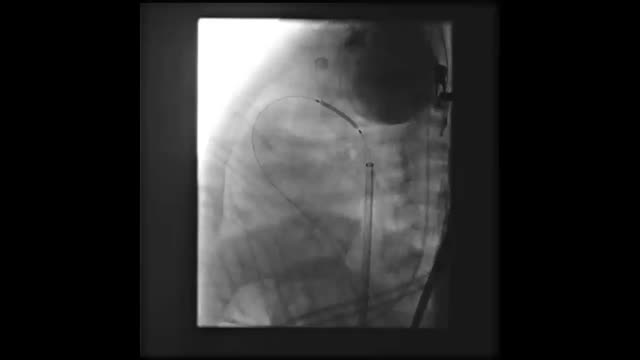

We present the case of a boy aged 15 months with a prenatal diagnosis of pulmonary atresia with intact ventricular septum who underwent pulmonary valve perforation and balloon valvuloplasty with an 8 mm balloon at 9 days post birth (Fig. 1A–D; Appendix B, videos 1–3). At 30 days, due to persistent desaturation, the decision was made to perform percutaneous ductal stenting, since this was less invasive compared to other techniques used to increase pulmonary flow. The procedure, guided by ultrasound, consisted in the delivery, via the left femoral artery and using a 5 F introducer, of a drug-eluting stent (Onyx Frontier, Medtronic, USA) measuring 4.5 × 12 mm to the ductus arteriosus (Fig. 1E and F; Appendix B, videos 4 and 5). Five days after the procedure, the patient experienced vomiting, and the abdominal ultrasound scan used for initial assessment revealed a mass in the left groin, with subsequent Doppler and angio-CT scans allowing visualization of a pseudoaneurysm at the level of the left common iliac artery (Fig. 2A–F).

(A) and (B) Right ventriculogram, anteroposterior and lateral views showing pulmonary valve atresia (7.5 mm ring). C) Pulmonary valvuloplasty performed with a TYSHAK MINI® (NuMED) 8 × 20 mm balloon catheter advanced on a 0.0014 coronary guidewire, which traversed the ductus arteriosus to the aorta supported by a gooseneck snare. (D) Angiographic confirmation of preserved pulmonary flow after valvuloplasty. (E) Lateral aortogram showing patent ductus arteriosus and filling of right chambers. (F) Aortogram following stent placement.